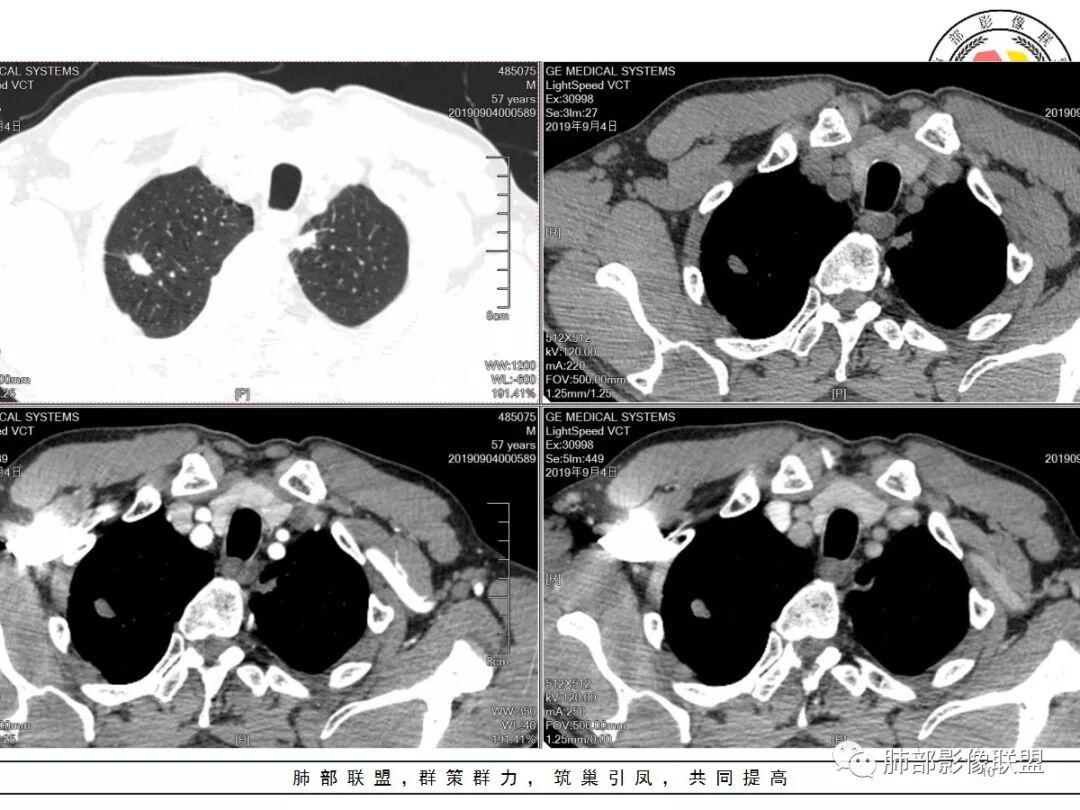

男,57岁,因“体检发现右上肺占位”入院。凝血常规、血常规、肾功能等均未见明显异常。

CT值:

平扫  18                          动脉期  28                      静脉期 41

双肺尖斑片状影及结节影,边缘平直为主,边缘可见胸膜牵拉,考虑结核,鉴别诊断腺癌,本病特点,多灶性,多态性,胸膜牵拉线纤细。

右上肺病灶,边缘平直,有卫星灶,强化不明显,考虑结核可能大

结核。右上肺结节密度均匀轻度强化,结节边缘清晰有小分叶,周围细长软毛刺,有卫星灶。左上肺近纵隔类似片状结节。

右肺尖结节边缘可见卫星灶,结节边缘平直凹陷、长毛刺,外观上有炎性结节的特点

增强扫描右肺尖结节强化不明确,但左肺尖后段结节出现了典型的环形强化

右肺结节影,边缘平直,有长索条与胸膜相连,左肺尖有条片状密度增高影,边缘清晰。左肺门斑点状钙化。考虑结核,老年人右肺上叶警惕瘢痕癌,建议复查。

右肺上叶结节灶,边缘膨隆,有毛刺,胸膜牵拉,轻度强化,左肺上叶结节灶环形强化,左肺考虑结核,右肺结节灶,不排除疤痕癌。

两肺上叶结节影,右肺结节边缘清晰,平直,有胸模牵拉,有卫星灶,强化不明显,左肺结节周边强化,两肺门淋巴结肿大,整体考虑结核。

右肺上叶结节,边缘部分膨隆,毛刺,内部有强化增粗血管影,边缘有空泡,胸膜有牵拉,考虑腺癌。鉴别结核。

右肺尖结节边缘可见分叶,结节边缘有毛刺,但左肺尖后段结节出现了典型的环形强化,考虑炎性病变,右上肺结节鉴别腺癌。还有患者食管上段壁明显增厚。

中年男性,查体发现,右肺肺上叶结节影,边缘平直收缩,周围有软毛刺,有胸膜牵拉,左肺上叶靠近纵隔不规则结节影,边缘平直内收,内有坏死。考虑良性病变可能性大,肺结核。鉴别肺癌合并结核。

中老年男性,体检发现双肺尖结节,边缘长索条,邻近胸膜粘连,病灶收缩力不太强,右肺尖病变周围少许卫星灶,增强后环形强化表现,首先考虑结核,治疗后复查

两上肺(右尖左尖后)都有小结节影,右肺尖结节边缘可见卫星灶,结节边缘平直凹陷、长毛刺,部分膨隆,增强扫描右肺尖结节强化不明确;左肺尖后段结节边缘平直凹陷,增强见环形强化。考虑结核可能性大,右上肺注意鉴别腺癌。

右上肺结节影,有平直收缩有膨隆,有长短毛刺,胸膜牵拉,增强扫描强化不明显或轻度强化,左上肺少许条索斑片状影,强化无特殊,纵隔肺门淋巴结钙化,肺气肿,肺大泡背景,老年男性,首先一元化都考虑结核,右肺上叶结节周围血管稍增粗,需要警惕合并肺癌。

男,57岁;图像质量好,1.25*10层=12.5mm,两个病灶,形态奇特,毛刺长,强化静脉期最高,增强稍微中心密度低一些,肺尖部位;

诊断:结核(多灶,2;多态,中心低、边界稍高);部分,肺尖;毛刺,长,非真正毛刺。

老年男性,体检发现右上尖段及左上尖后段不规则结节影,右上尖段结节边缘长毛刺、似见卫星灶、局部胸膜牵拉,增强无明显强化。左上结节环形强化,考虑结核。老年男性,肺气肿背景,注意排除右上肺腺癌。

右肺上叶尖段结节,边缘平直收缩,周围有细长毛刺,有卫星灶,符合结核,但有静脉期轻度强化,结核应该没有强化,肺癌?

双肺尖结节 左肺边缘收缩 环形强化 右肺病灶上部边缘平直及长毛刺 下部分边缘膨隆及分叶 细短毛刺 好像有局灶强化 不除外结核基础上的瘢痕癌可能

倾向二元,左肺上叶病灶环形强化支持结核,右肺上叶结节平直、部分稍膨隆,胸膜牵拉征,部分毛刺粗短、支气管似乎边缘截断,临近小叶间隔增厚,延迟强化,密度似乎不均匀,内见小点状坏死,腺癌放前面,炎性放待排。

左上叶结节,环形强化,考虑肉芽肿病变,结核可能,右上叶结节,中度强化,有长毛刺,胸膜牵拉,有刀切征,考虑肉芽肿病变,腺癌待排,建议抗炎后复查或穿刺活检。

老年男性,体检发现,右肺上叶尖段类圆形结节

小叶中心型肺气肿背景,一般提示吸烟

周围有类似小结节

根据周围常规:我们要考虑结核的可能

我们再看右肺上叶这个较大病灶主体

类圆形,浅分叶

胸膜凹陷

血管纠集

局部凸起

强化幅度超过20HU

边缘平直

有炎性的特点,但是确实存在恶性征象

我觉得恶性最起码不能排除,要考虑,最起码要建议临床干预

1.应该是双肺上叶多发结节,散在大小不等,密度不均,左上纵隔旁病灶环形强化,似乎都符合结核灶。

2.焦点在乎右肺上叶那个有点另类、有点儿一本正经的结节,密度均匀,未见支气管进入,部分圆隆浅分叶,长毛刺或棘状突起,胸膜有点牵拉,像个特立独行的新生物吗?

3.最不支持腺癌的一条是强化程度太轻。此外分叶不典型,还有那条牵张于肺表面的长长的细线影,不大像是在牵拽。

4.小结节新生物不大容易观察到液化坏死,如观察到液化坏死更容易想到的也是结核。